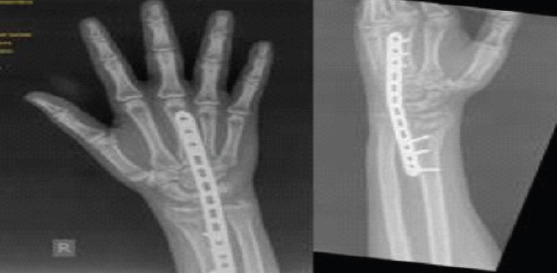

Abstract Image